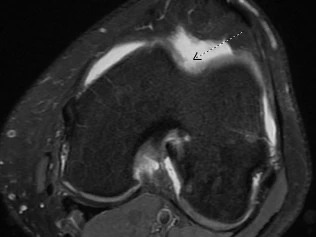

Your symptoms (pain, swelling, mechanical symptoms) may indicate to your physician if cartilage damage is to blame. X-rays and advanced imaging, including MRI, can show areas where cartilage has worn away.

An MRI from the same patient's knee. The arrow points to the area on the patella (kneecap) where healthy, intact cartilage is missing.

An MRI from the same patient's knee. The arrow points to the area on the patella (kneecap) where healthy, intact cartilage is missing.How Can I Protect My Joint Cartilage?